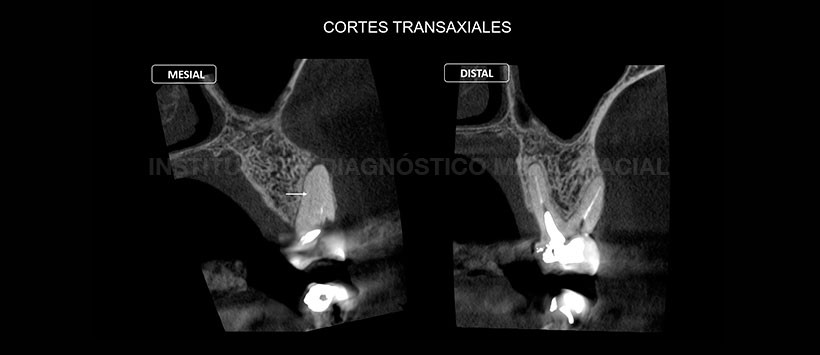

A la evaluación de la tomografía volumétrica de haz cónico (Figura 2 y Figura 3), se evidencio que la pieza 26 presenta un cuarto conducto sin obturar (mesiopalatino), motivo por el cual cuando se evaluó en una segunda vista transaxial y tangencial (Figura 4), encontramos que dicho conducto conllevaba a la formación de proceso osteolítico apical.